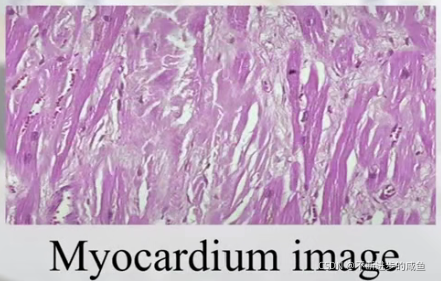

(5)显微图像:

上图,心脏肌肉的显微照片,这是临床中经常应用的一类称为活检对图片,当我们怀疑组织的某一部分有病变的时候,通过穿刺的方法,在身体组织、器官表面进行采样,得到组织碎片,通过在显微镜进行放大,进行分析——病理诊断